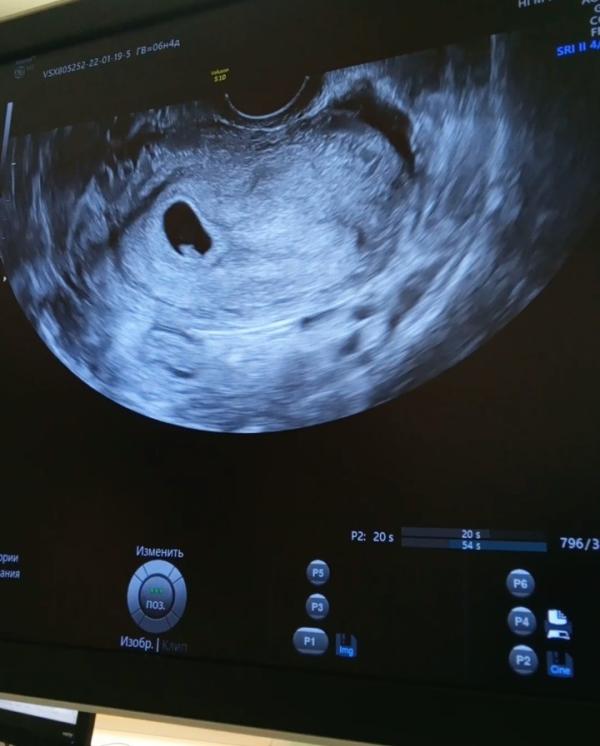

На сроке 6 недель и 4 дня ходила на первое УЗИ в ЖК для постановки на учёт. Беременность маточная, эмбрион 6,8 мм, сердцебиение есть.❤️ Увидели гипертонус, ретрохориальную гематому и сказали, что шейка матки 30 мм коротковата для такого срока. Гинеколог сказала, что на учёт поставить не может, нужно ложиться на сохранение, дала направление в 3 роддом. Лежу с вечера среды на сохранении. В роддоме при поступлении УЗИ переделали, подтвердили, что нужно госпитализироваться.